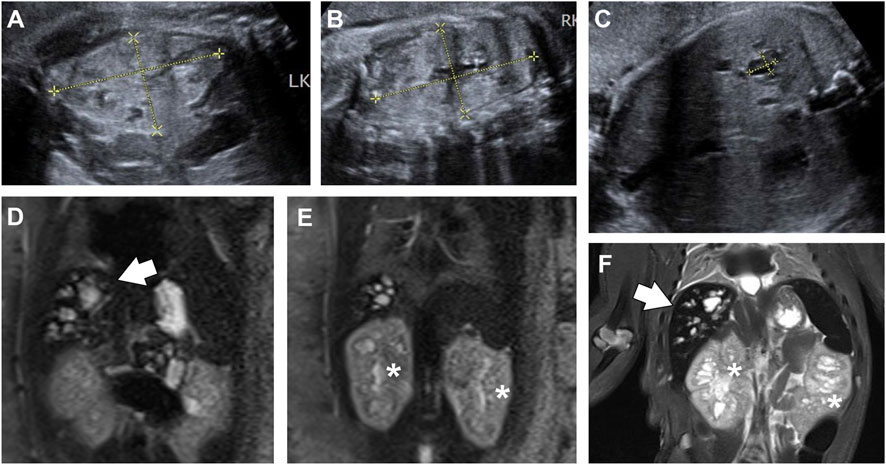

A 26-year-old primigravida presented to our hospital for ultrasound consultation due to increased echogenicity in the fetal kidneys and oligohydramnios at 38 weeks of gestation. At 39+2 weeks of gestation, ultrasound examination revealed several anechoic cystic lesions in the right lobe of the fetal liver (Figure 2C). Color Doppler did not show flow within the lesions. Both kidneys were enlarged and echogenic, with no corticomedullary differentiation (Figures 2A,B). Oligohydramnios was noted, with an amniotic fluid depth of 2.3 cm and an amniotic fluid index of 6.1 cm.

Figure 2. View of fetal abdomen before (A–E) and after birth (F). (A-C) Ultrasound images of fetal kidney (A,B) and liver (C) at 39+2 weeks of gestation. Both kidneys ((A,B); left, 6.28 cm × 3.57 cm; right, 6.67 cm × 3.65 cm) were enlarged and echogenic, with no corticomedullary differentiation. The right lobe of the liver (C) showed diffuse cystic structures, one of which was 1.03 cm × 0.74 cm in size. (D,E) T2-weighted MRI image of fetal abdomen at 39+6 weeks. The fetal liver (D, arrows) was hyperintense on T2-weighted sequences, showing multiple cystic and tubular structures. Both kidneys [(E), asterisks] were enlarged and heterogeneous, with numerous micro cysts. (F) T2-weighted MRI image of the baby, showing dilated intrahepatic biliary ducts (arrows), and slightly enlarged kidneys (asterisks) with cystic structures.

At 39+6 weeks, an MRI study was performed. T2-weighted sequences revealed multiple cystic and tubular dilatations of varying sizes within the hepatic parenchyma (Figure 2D). Both kidneys were enlarged and exhibited numerous cystic structures that appeared hyperintense on the T2 sequence (Figure 2E). The baby was delivered vaginally at term but died a few days later. Postnatal T2-weighted MRI confirmed the presence of similar findings in the kidneys and liver (Figure 2F). The couple refused autopsy, so pathological confirmation of CHF was not obtained. Based on these findings, a diagnosis of CD/CS with ARPKD was suggested.